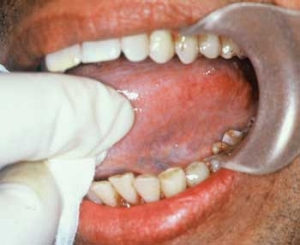

These products are highly addictive, producing a sense of euphoria. With the added tobacco used by many consumers, the oral cancer risk is more increased with areca and tobacco combinations (see Figure 3). Users of these products can commonly be identified by the red/orange or brown intraoral pigmentation on the tissue and teeth. Over time, the wearing away of tooth structure from both chemicals and friction can be observed (Figure 4).

Figure 4: Note the pigmented tissue.